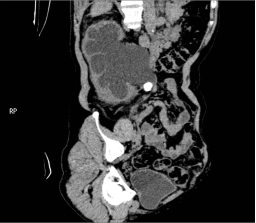

入院后,三维CT发现患者双侧输尿管结石,右肾盂输尿管连接处狭窄,右肾严重积水,左肾也因结石梗阻导致肾盂输尿管积水。肌酐1284.5μmoI/L,已经达到急性肾功能不全(尿毒症期)。王春阳教授立即为患者进行超声引导下右肾穿刺造瘘,改善患者肾功能,并制定拟行机器人辅助腹腔镜下双侧输尿管切开取石术+机器人辅助腹腔镜下右侧肾盂成型肾盂输尿管再吻合术,决定一次手术解决目前导致患者肾脏积水的全部问题。

王春阳教授介绍,仅利用一次手术同时处理患者全部问题,大大增加手术难度,但能减轻患者的痛苦和费用。对于结石大、梗阻明显、结石坎顿的病人,为及时解决梗阻,挽救肾功能,可选择输尿管切开取石。传统的输尿管切开取石手术疗效可靠,但患者手术创伤大,恢复慢,住院时间长。运用机器人辅助腹腔镜下行输尿管切开取石术不切断肌肉,不损伤较大血管神经,手术直视下进行,术野可放大10倍,手术损伤小,出血少,恢复快。同时该病人CT中表现出右侧肾盂输尿管连接部狭窄,切开取石后行右侧肾盂成形术,去除狭窄段,对肾盂输尿管连接部重新塑形,显著解除梗阻。